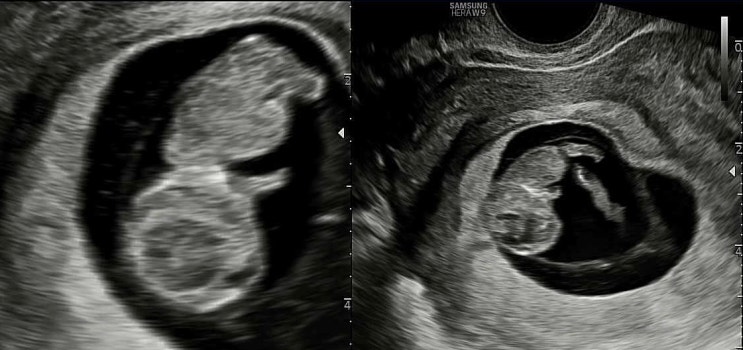

13주차 초음파 성별확인 공주님 feat. 입체 초음파 잘 찍는 팁

13주차 2일째 되는 날 1차 기형아 검사를 받으러 산부인과를 방문했답니다. 1차 검사는 11~13주 사이에 받...